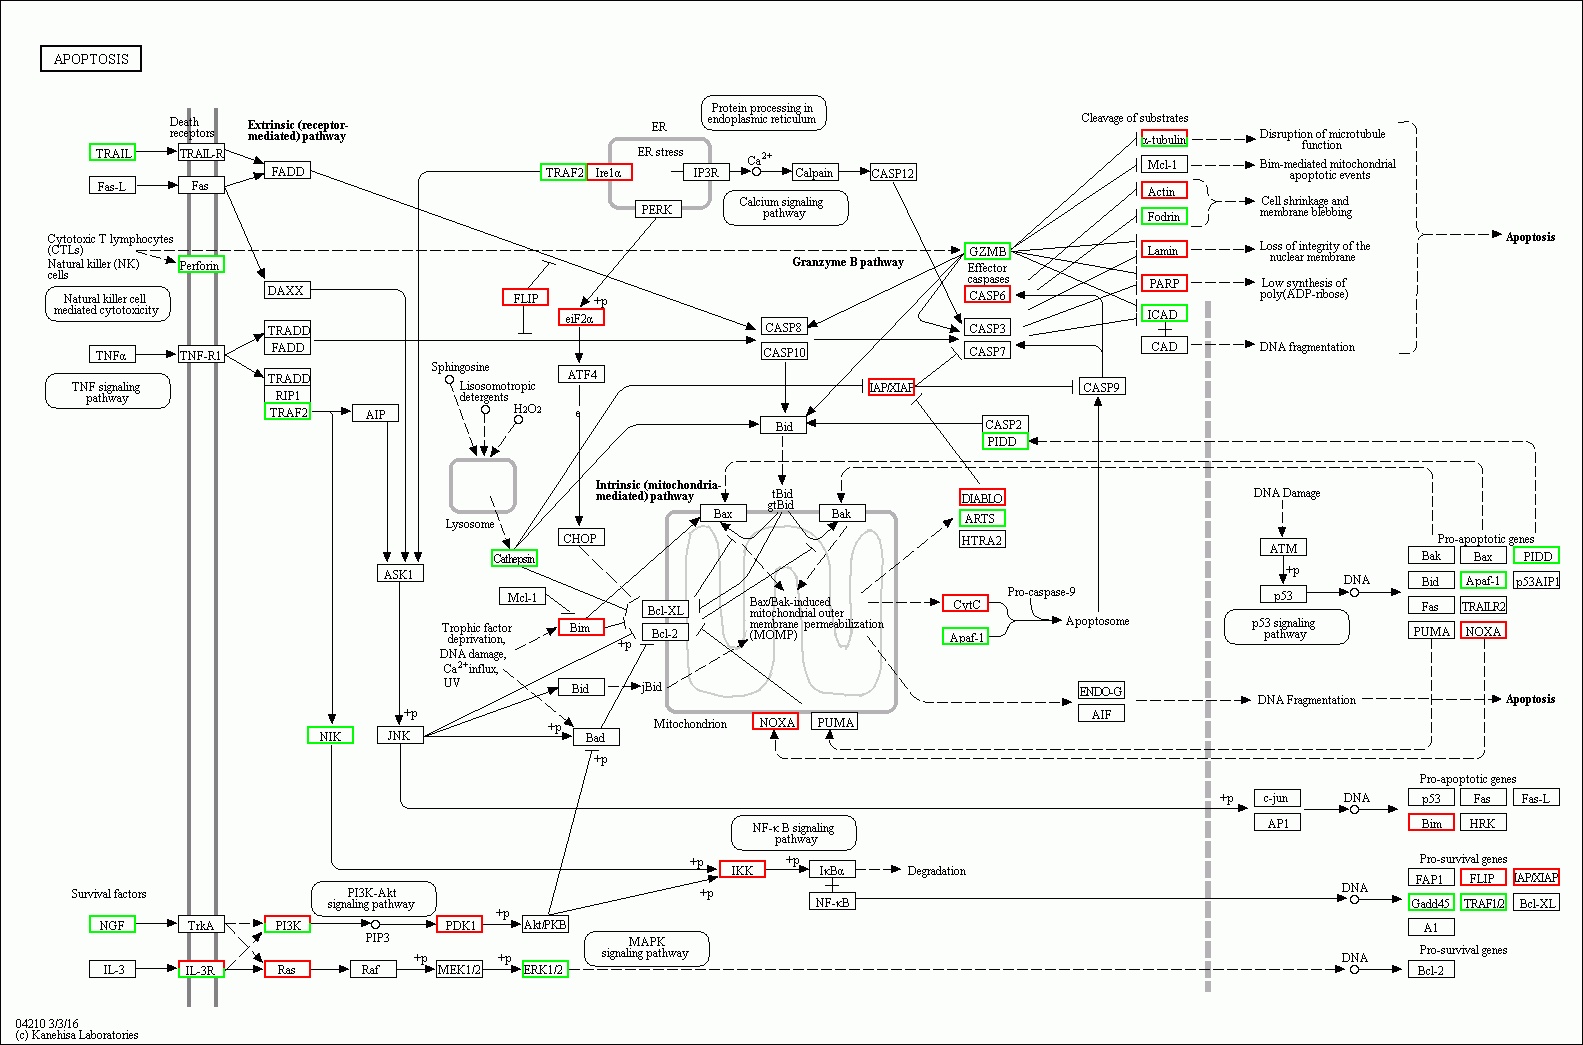

2 结果48 h各组病理结果,对照组脾组织结构正常(见图 1A )。脓毒症组脾组织见白髓结构破坏,红白髓交界模糊,多量组织细胞浸润,红髓充血(见图 1B)。差异mRNA的Volcano-plot分布图(见图 2)。相比于对照组,24 h时脓毒症组脾组织mRNA表达上调的有1 030个,下调的有935个[5];48 h组表达上调的有1 354个,下调的有1 763个。差异mRNA的聚类情况(见图 3)。GO功能分类结果(见图 4)。脓毒症大鼠脾组织部分通路相关基因表达情况(见图 5、6):脓毒症大鼠24 h,48 h脾组织关于细胞因子及其受体相互作用通路相关基因的分布图(见图 7,图 8)。脓毒症大鼠24 h,48 h脾组织关于细胞凋亡相关通路的基因分布图(见图 9,图 10)。

| 图 9 脓毒症大鼠24 h组 |

| 图 10 脓毒症大鼠48 h组 |

(2)脓毒症晚期脾组织相关细胞的凋亡系脓毒症晚期脾功能障碍的原因之一。从图 9-10可以看出,在细胞凋亡相关通路中,脓毒症大鼠24 h脾组织mRNA表达上调,48 h表达下调有1个:Gadd45。24 h表达上调,而48 h正常表达的基因有5个:IL-3R、IκBα、a-tubulin、c-jun、AP1。24 h正常表达,而48 h转为表达下调的基因有9个:TRAIL、NGF、TRAF2、NIK、Cathepsin、GZMB、ICAD、Apaf-1、TRAF1/2。24 h正常表达,而48h转为表达上调的基因有10个:Ras、PDK1、Irelα、eiF2α、IKK、CASP6、DLABLO、CytC、PARP、NOXA。脓毒症大鼠24 h脾组织mRNA表达下调,而48 h转为表达上调的基因有1个:Actin。24 h表达下调转为正常表达的有1个:fas-L。脓毒症晚期大鼠脾组织细胞凋亡相关通路中的基因表达紊乱,可能是晚期脾功能障碍的原因之一,特别是胞膜空泡化相关基因Actin从下调转为上调,促凋亡相关基因NOXA从正常表达转为上调,促生存基因Gadd45从表达上调转为下调,促生存基因TRAF1/2从正常表达转为下调直接促进相关细胞的凋亡。